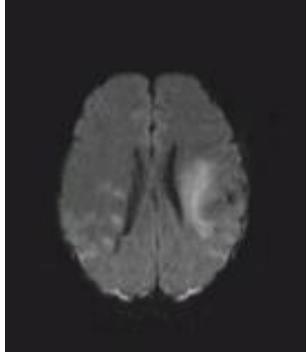

• 肿瘤样脱髓鞘病变报道3例

2023, 48(5):614-617. DOI: 10.13406/j.cnki.cyxb.003183

摘要 (95) HTML (24) PDF 1.29 M (241) 评论 (0) 收藏

摘要: